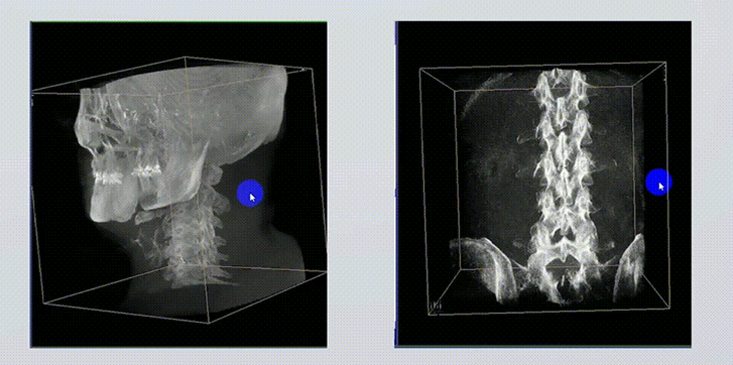

1、術中實時三維成像

術中三維成像和橫斷面圖像提供多角度的手術診斷信息,輔助醫生進行術中評估判斷,諸如骨折復位情況和內植入螺釘的尺寸和位置,輔助手術更好地完成。

3D成像技術

2、三維成像視野大

提供更大的術中三維成像視野,采集更多圖像信息,可一次拍全全段頸椎、全段腰椎、七節胸椎、雙側骶髂關節、股骨頭及單側盆骨。